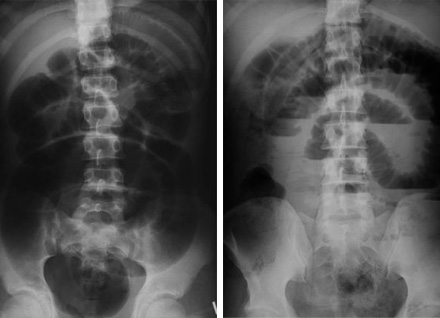

Plain abdominal radiographs (left-supine and right erect) demonstrating small bowel obstruction.